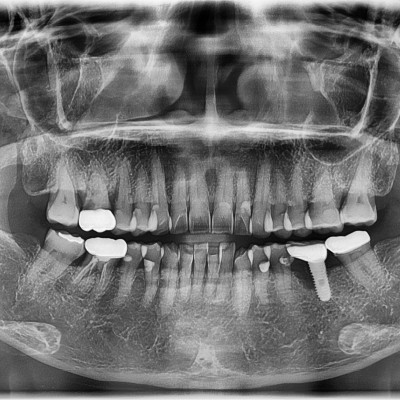

임플란트 재수술 #37 타원 임플란트 제거 후 임플란트 수술+치조골이식술 시행하였습니다.